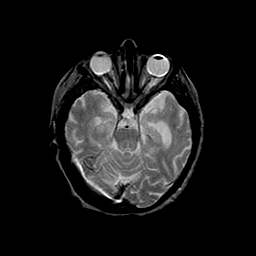

Basal Ganglia Calcification: T2-weighted MR -- Slice #6

[Home][Help][Clinical] Slice 6